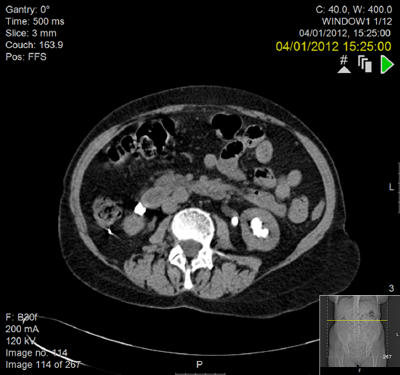

A 59-year-old woman with a right-sided duplex ureter presented with right flank pain and confirmed recurrent urinary tract infection and a right lower pole calculus lying peripherally with very little overlying cortex.

PCNL was considered but a laparoscopic approach was preferred due to the radiological lack of overlying cortex. A four-port retroperitoneal laparoscopic approach was utilised.

The stone was identified in the lower pole and extracted via a nephrotomy incision but fell into the retroperitoneum and could not be found. The lower pole cortex was closed over with 3-O interrupted PDS sutures and a 20 Robinson’s drain placed into the retroperitoneum.

The patient is pain free with no further urinary tract infections postoperatively. The stone is still visible in the retroperitoneum on CT scanning but has caused no further problems 10 years on from surgery.

Preoperative IVU and CT demonstrating very little overlying renal cortex in duplex system.

Seven years postoperatively. New left staghorn calculus and right-sided fragment demonstrated outside the kidney.